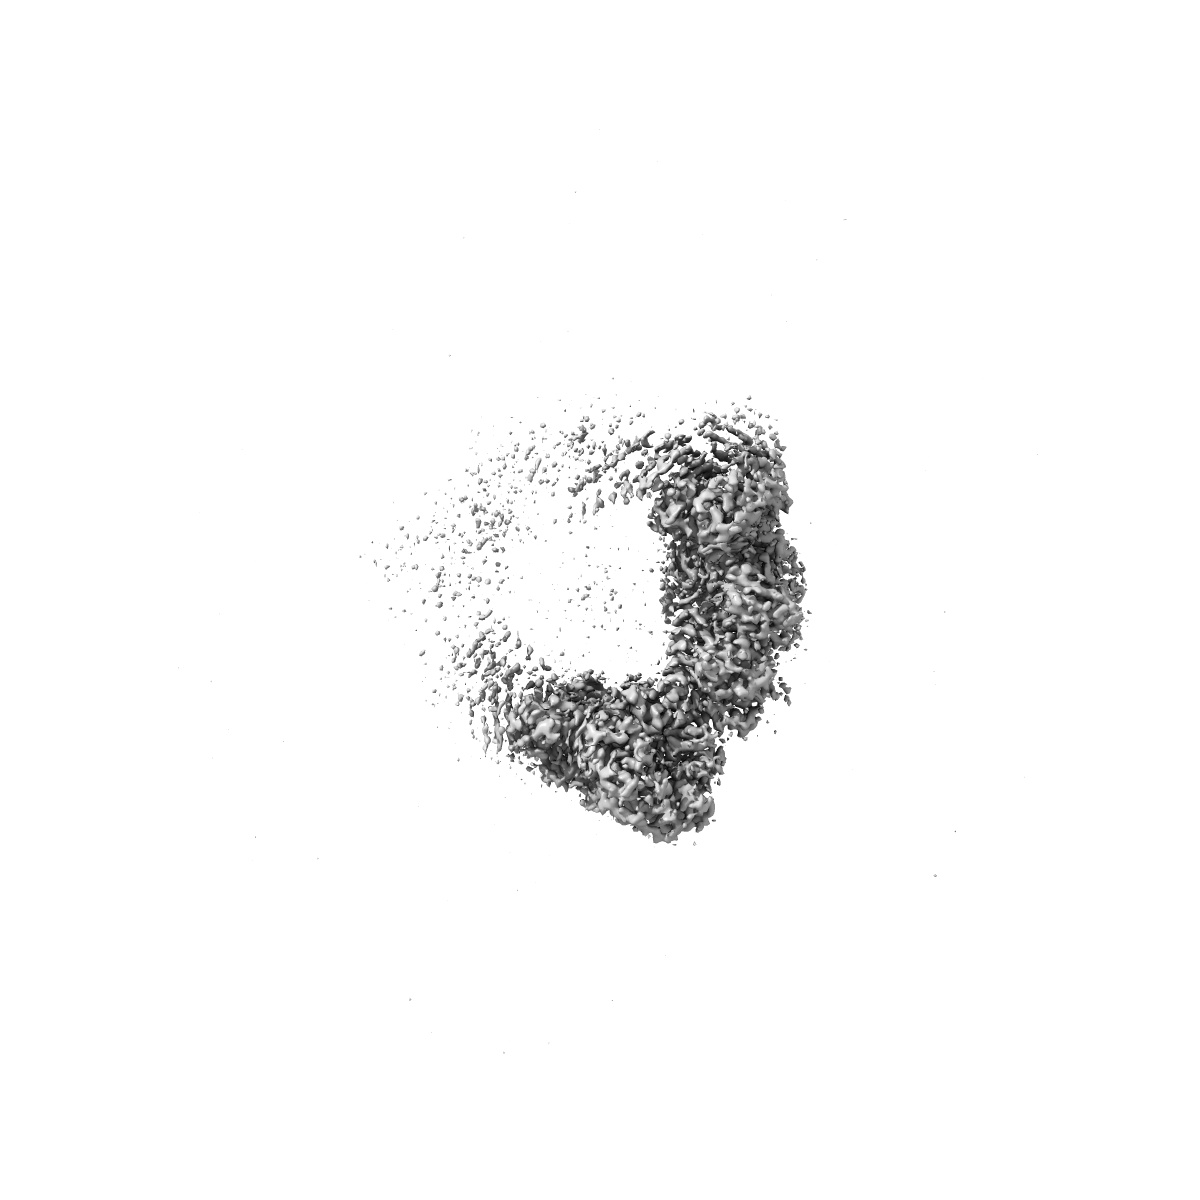

Structure of C-terminal half of LRRK2 bound to GZD-824

EMD-41756

Single-particle

2.9 Å

3D View Gallery

Sample Organism: Homo sapiens

Sample: Complex of LRRK2-RCKW with GZD-824

Fitted models: 8tze

Deposition Authors: Villagran-Suarez A, Sanz-Murillo M, Alegrio-Louro J, Leschziner A

Inhibition of Parkinson's disease-related LRRK2 by type I and type II kinase inhibitors: Activity and structures.

Sanz Murillo M , Villagran Suarez A , Dederer V , Chatterjee D, Alegrio Louro J , Knapp S , Mathea S , Leschziner AE

(2023) Sci Adv , 9 , eadk6191 - eadk6191